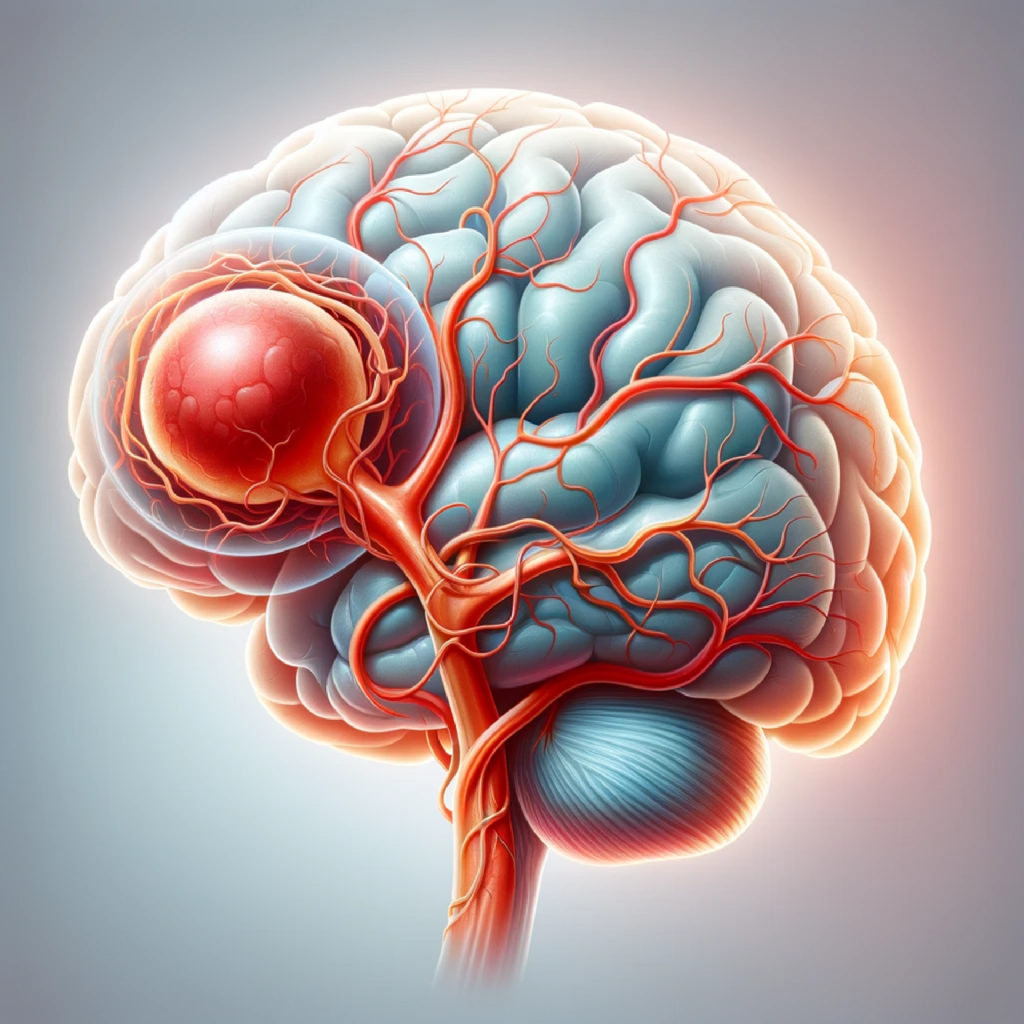

Səbəbləri Genetik Faktorlar: Bəzi AVM halları genetik olaraq meydana gəlir. Doğuşdan Gələn A ...

Səbəblər və Risk Faktorları: Beyin anevrizmalarının səbəbləri tam olaraq bilinməsə də, genetik fa ...